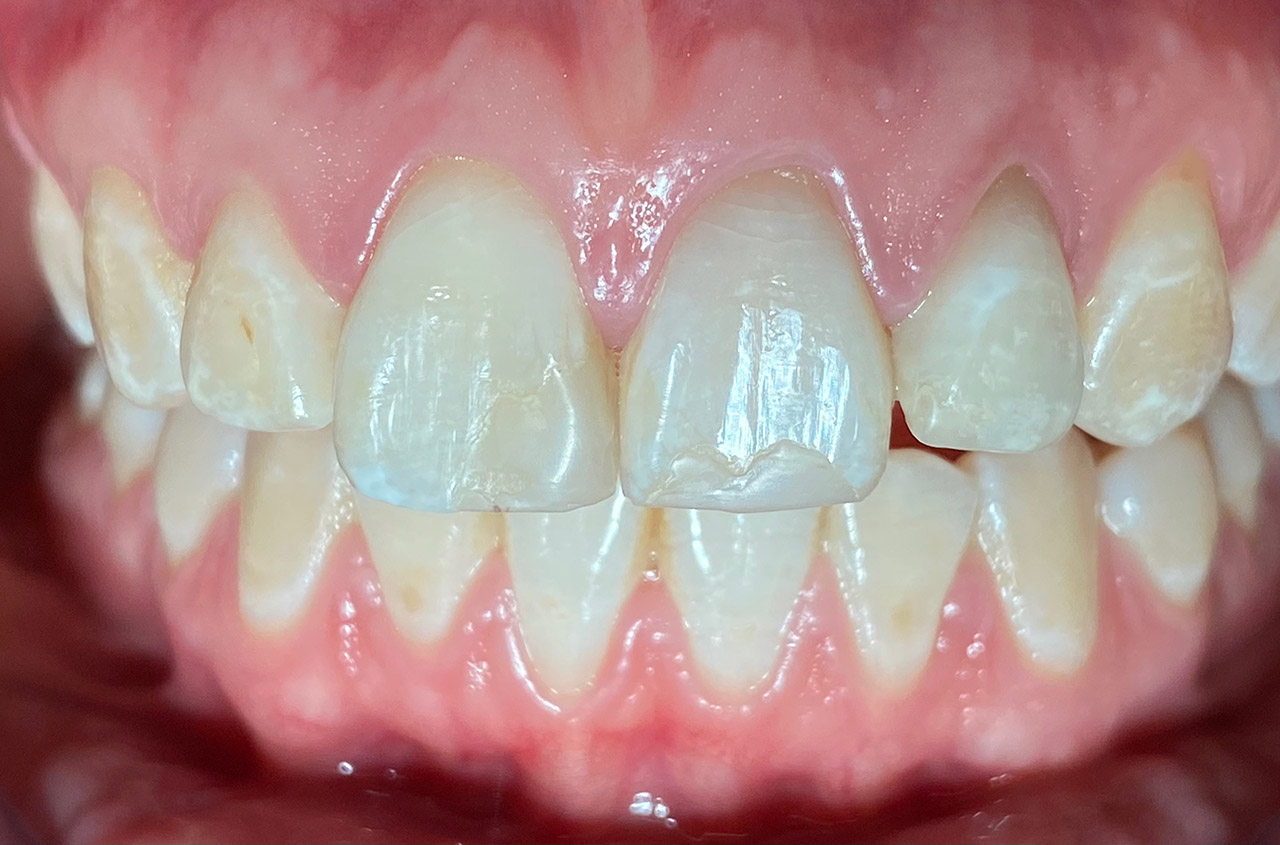

Traumatologie und Endodontie:

Nach Unfall/Sturz mittlerer Schneidezahn auf Gingivaniveau abgebrochen, Pulpa weit eröffnet, beide Nachbarzähne ebenfalls frakturiert.

Erstversorgung: Pulpektomie der Kronenpulpa, MTA, provisorischer Verschluß mit rosa Glasionomerfüllung.

Wiederaufbau der Nachbarzähne mit mitgebrachten (plus 1 Stein) Zahnstücken mit Kunststoff ergänzt und adhäsiv verklebt.

2. Schritt nach Aushärtung von MTA: Entfernung der Kronenpulpa im Bruchstück zur Vermeidung von Verfärbung, Füllung mit Kunststoff.

Adhäsives zementieren des abgebrochenen Zahnstücks.